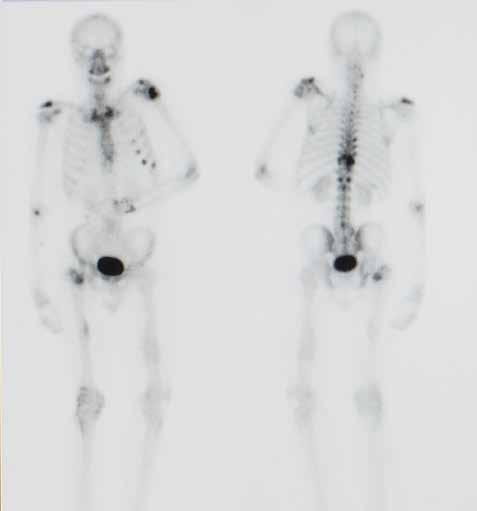

Il s'agit d'un test très spécifique pour voir si le cancer s'est propagé à l'os. Si la tumeur se propage, c'est souvent à l'os en premier lieu. Tout comme le PET scan, ce scanner est réalisé à l'aide d'une substance radioactive qui est injectée, de sorte que les endroits présentant une activité accrue peuvent être visualisés.

Exemple de résultat d’une scintigraphie osseuse chez une personne présentant des métastases dans les os (visibles sous forme de taches sombres).